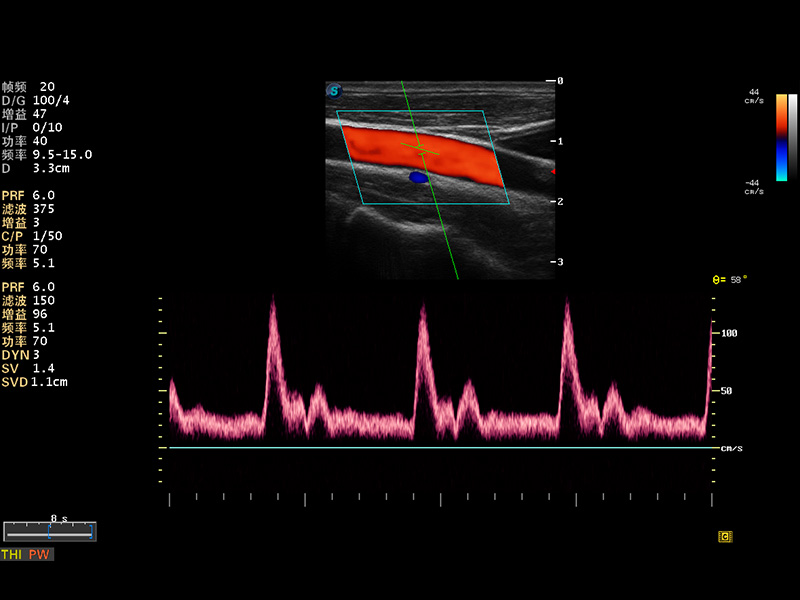

S8 EXP便携式彩色多普勒超声诊断仪是1xBET研发的高端全身应用型便携彩超。高通道的VIS平台融合可视化(Visual)、智能化(Intelligent)和人性化(Smart)的特点,配以1xBET自主研发生产的探头大家族,使您能够快速、准确的获得病人信息,提高工作效率的同时减轻疲劳。

成像技术

多波束形成器